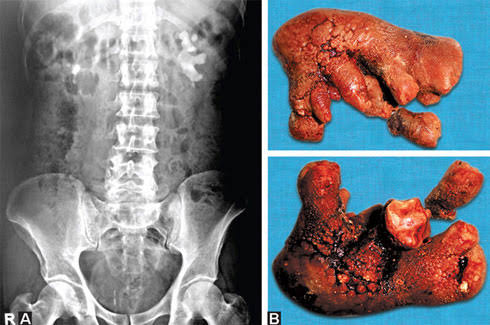

65 風吹けば名無し 2022/04/13(水) 01:04:16.76 ID:3IS5jfn+0

124 風吹けば名無し 2022/04/13(水) 01:19:04.92 ID:oOHy+eLs0

>>65

これ手術するの腎臓真っ二つにするん?二つに割ってまたくっつけて機能的には回復するもんなん?

これ手術するの腎臓真っ二つにするん?二つに割ってまたくっつけて機能的には回復するもんなん?

129 風吹けば名無し 2022/04/13(水) 01:19:35.39 ID:3IS5jfn+0

>>124

取ったり何か縫い合わせてそのままにしたり色々やで

取ったり何か縫い合わせてそのままにしたり色々やで

90 風吹けば名無し 2022/04/13(水) 01:10:07.20 ID:9aLscr1Y0

これワイらの身体にも可能性あるんか?

97 風吹けば名無し 2022/04/13(水) 01:12:21.51 ID:3IS5jfn+0

99 風吹けば名無し 2022/04/13(水) 01:13:06.92 ID:sqz+6fDF0

>>97

赤黒くなってるのはこわいからやめろ😡

赤黒くなってるのはこわいからやめろ😡